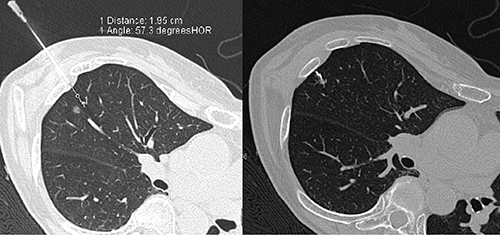

胸腔鏡補助下で外科的切除を行う場合,病変部が微小で体表に近いものについては,術前にCTガイド下でフックワイヤを使用し経皮的にマーキングを行う(図1)。しかし,病変部が深部に存在する場合,経皮的なマーキングでは,隣接する他臓器との解剖学的位置関係から,気胸や出血,肺の血管が大きく損傷されることで起こる空気塞栓などの合併症に注意を要するため,穿刺が非常に困難となる。そこで,胸腔鏡下にて病変部を肉眼的に特定することを目的として,術中に気管支鏡により気管支の内側から光源によるマーキングを行うことが有効と考える。

図1 フックワイヤを使用した経皮的マーキング